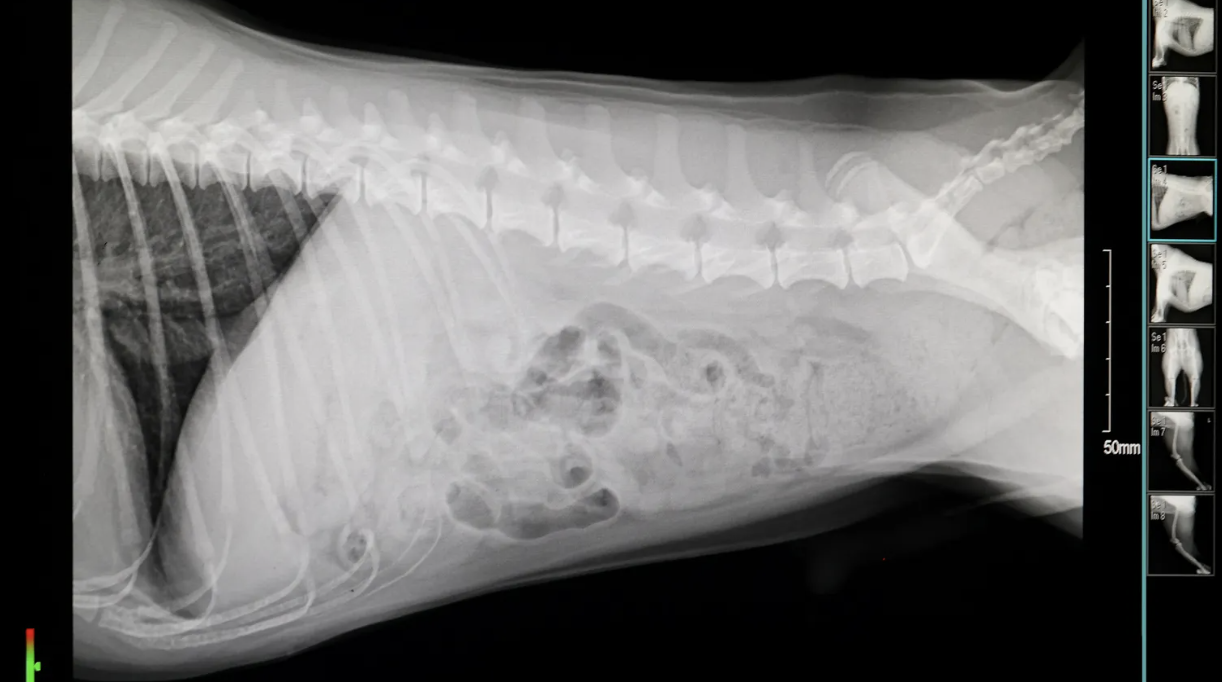

SK텔레콤과 코벳이 협력하여 개발한 엑스칼리버는 반려동물의 엑스레이 사진을 AI로 분석해 수의사의 질병 진단을 돕는 대표적인 진단 보조 서비스입니다. 단순히 이미지를 개선하는 것을 넘어, 의심할만한 질환 목록과 각 질환으로 진단될 확률을 수치로 정리해 보여줍니다. 이는 영상 전공의가 없는 1차 병원이나, 진단에 대한 확신이 필요한 순간에 'Second Opinion' 역할을 수행합니다. 현재 1,200여 개 동물병원에 보급되어 임상 현장에서 그 효용성을 입증하고 있습니다.

• 임상 적용점: 영상 판독 업무가 과중하거나, 보호자에게 객관적인 수치를 근거로 진단 결과를 설명하여 신뢰도를 높이고자 하는 병원에 적합합니다.